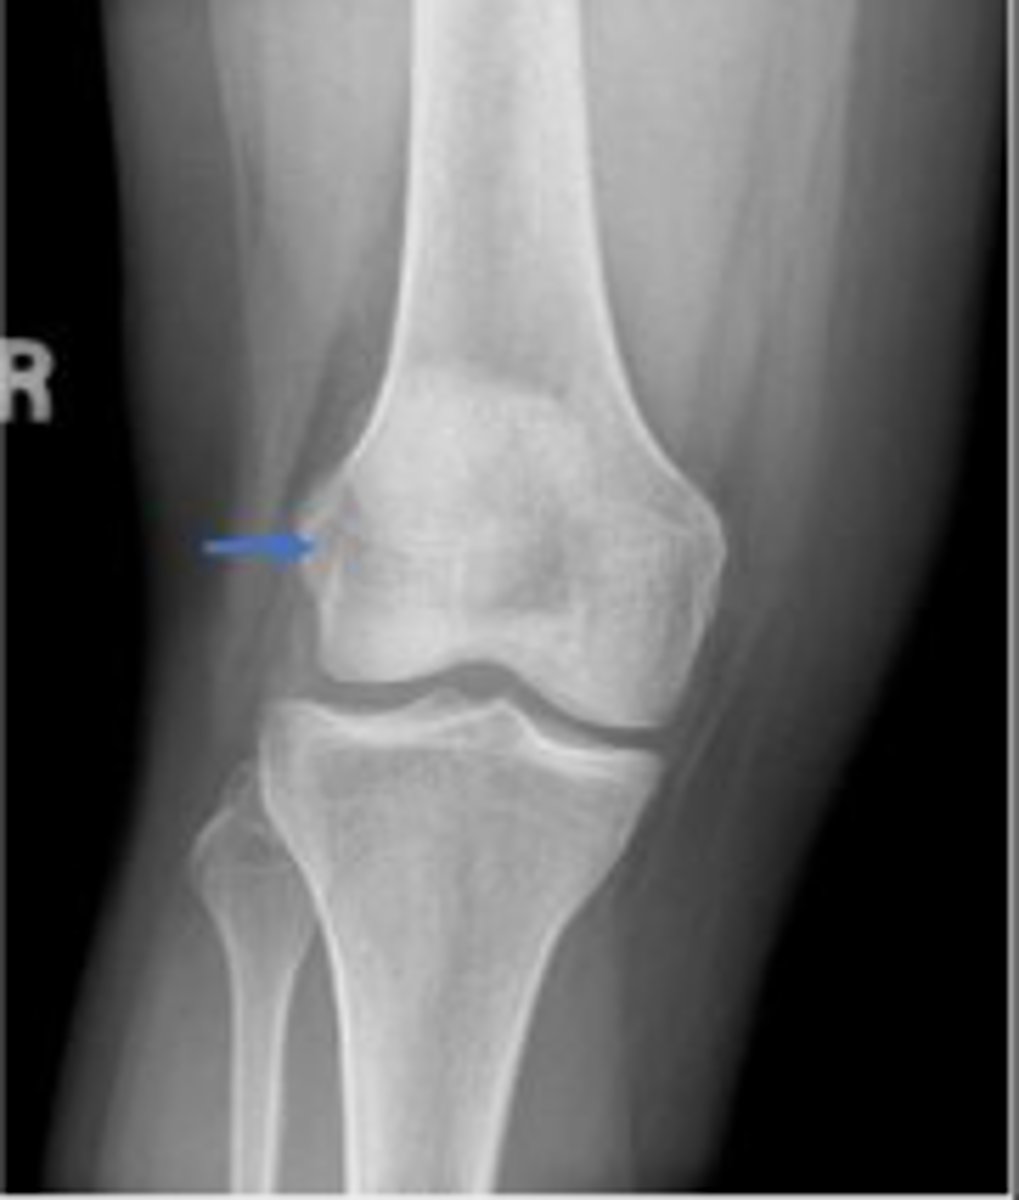

Right adductor tubercle

What tubercle is pointed to by the arrow?

Lateral epicondyle of the right femur

What is the arrow pointing to?